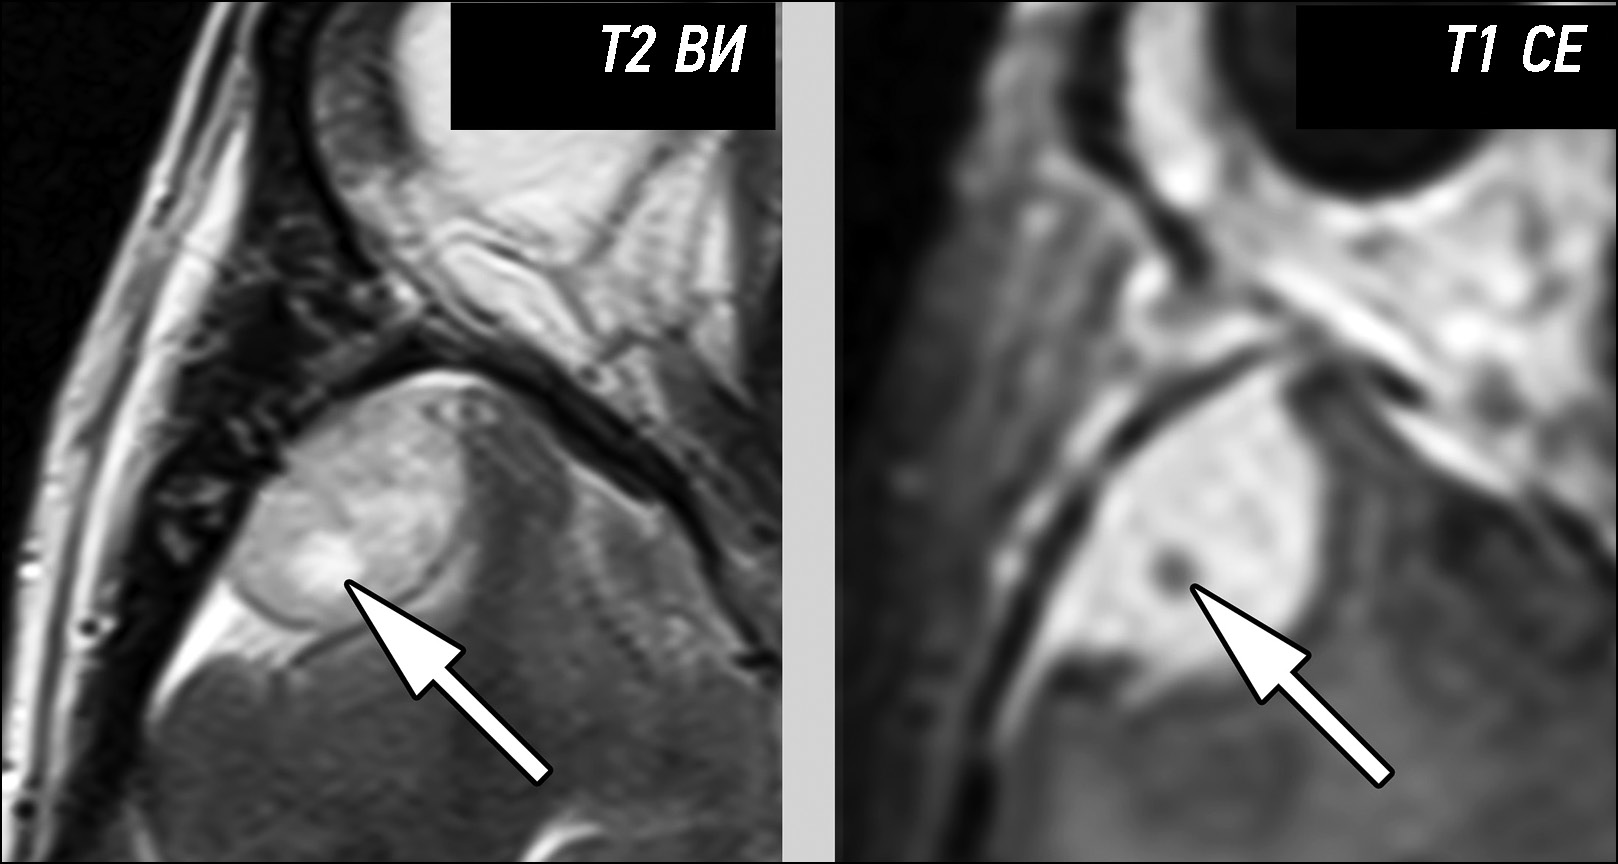

年轻患者左侧阴囊疼痛的睾丸缺血诊断:附睾炎的潜在致命并发症

在极少数情况下,急性附睾炎会伴有睾丸缺血和梗塞。 通过临床症状和影像学检查结果很难区分附睾炎和睾丸扭转。在本文中,我们努力扩大用于快速准确鉴别诊断的放射治疗诊断方法的数字图像库。本病例强调了全面放射检查的重要性,以及采用跨学科方法做出准确诊断的必要性。一名24岁的男子因两周前出现左侧睾丸剧烈疼痛而来到医院就诊。据患者称,已经有一段时间出现射精疼痛、性交疼痛、阴囊发红/肿胀、生殖器发炎、恶寒、腹股沟淋巴结肿大、排尿困难和阴囊疼痛。在泌尿科医生的建议下,接受了超声检查和核磁共振成像检查。 影像学检查显示左侧睾丸缺血。根据病史,怀疑患有慢性睾丸附睾炎。由于缺血范围有限,患者无需进行左侧睾丸切除术。 接受了药物治疗。此外,患者还被诊断为左侧精索静脉曲张。对不同磁共振成像序列获得的图像进行了仔细研究。本文描述了一例罕见的睾丸附睾炎病例,这是附睾炎的一种潜在危险并发症。为避免严重后果,当阴囊突然剧烈疼痛时,应考虑到这种并发症的可能性。此案例的描述,能够优化患者的管理方法,并避免不必要的干预。